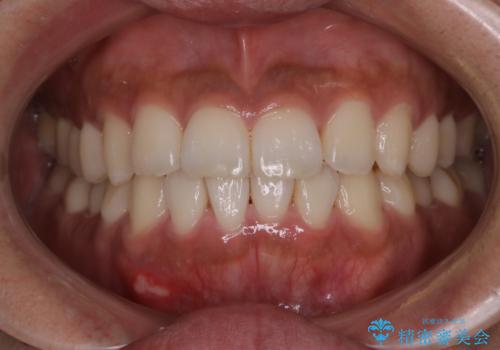

[ マウスピース矯正 ] 前歯のねじれを治したい

![[ マウスピース矯正 ] 前歯のねじれを治したいの症例 治療後](https://seimitsushinbi.jp/wp/wp-content/uploads/2022/01/IMG_0069-500x350.jpg?v=1641870943)